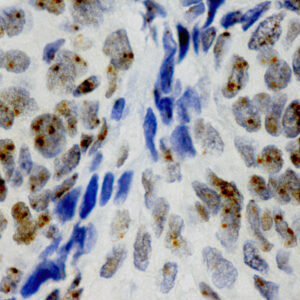

BioGenex offers fluorescein-labeled oligonucleotide probes to detect DNA or RNA using In situ Hybridization (ISH). These probes allow quantitative detection of specific DNA/RNA sequences in their native form within the cells of formalin-fixed paraffin-embedded (FFPE) tissue sections. These probes offer reliable, highly sensitive, and easy-to-perform DNA and RNA ISH assays when used with the BioGenex ISH Detection Systems.